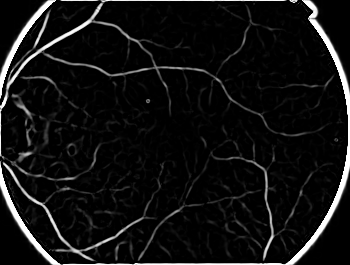

這個算法我測試確實對血管圖像的提取效果比較顯著,在貼幾個圖片。